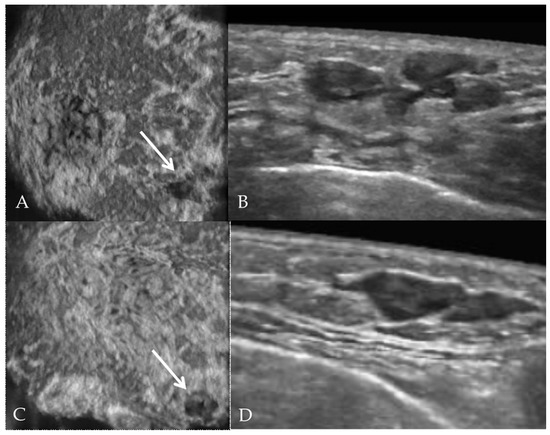

- Lyou, C.Y.; Yang, S.K.; Choe, D.H.; Lee, B.H.; Kim, K.H. Mammographic and sonographic findings of primary breast lymphoma. Clin. Imaging 2007, 31, 234–238. [Google Scholar] [CrossRef] [PubMed]

- Nicholas, S.; Richard, G.B. Sonoelastography of Breast Lymphoma. Ultrasound Q. 2016, 32, 208–211. [Google Scholar] [CrossRef]

- Hoang, J.T.; Yang, R.; Shah, Z.A.; Spigel, J.J.; Pippen, J.E. Clinico-radiologic features and management of hematological tumors in the breast: A case series. Breast Cancer 2019, 26, 244–248. [Google Scholar] [CrossRef] [PubMed]